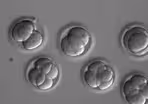

For the first time in the U.S., a human embryo has been successfully edited.

For the first time in the U.S., a human embryo has been successfully edited to correct an inherited condition. By snipping out the gene that causes a specific heart disease, scientists also ensured the disease could not be passed down. But the milestone raises significant scientific and ethical questions. Hari Sreenivasan speaks with Jessica Berg of Western Case Reserve University Law School.